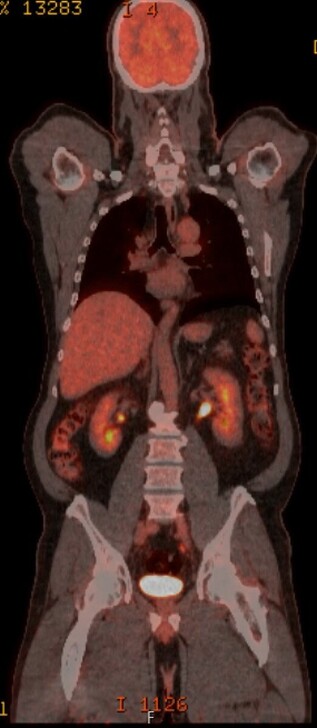

@TumorBoardTues @tompowles1 @MPishvaian @JohnEbbenMDPhD 3/15

❌PET scan prior to✂️

🩻PET lacks sensitivity in MIBC (70% in prior study n=43)

📚@adamkibel_uro pubmed.ncbi.nlm.nih.gov/196520

clinically negative CT + bone scan, PET/CT had SNS of 70% in MIBC

🧑🏻‍⚕️🤝👴🏽 4 cycles neoadju gem+cis